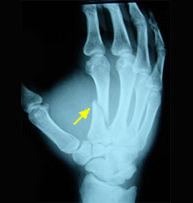

Fractures of the metacarpals and phalanges account for 10% of all fractures. More than half are due to occupational injuries. It is unquestionable the importance of a hand in our daily life and it goes without saying that proper recovery requires an exquisite knowledge of anatomy and biomechanics in order to properly treat hand injuries. Stiffness is very common in lengthy immobilizer treatments. To avoid stiff joints we propose minimally invasive techniques that allow early reincorporation in daily activities.